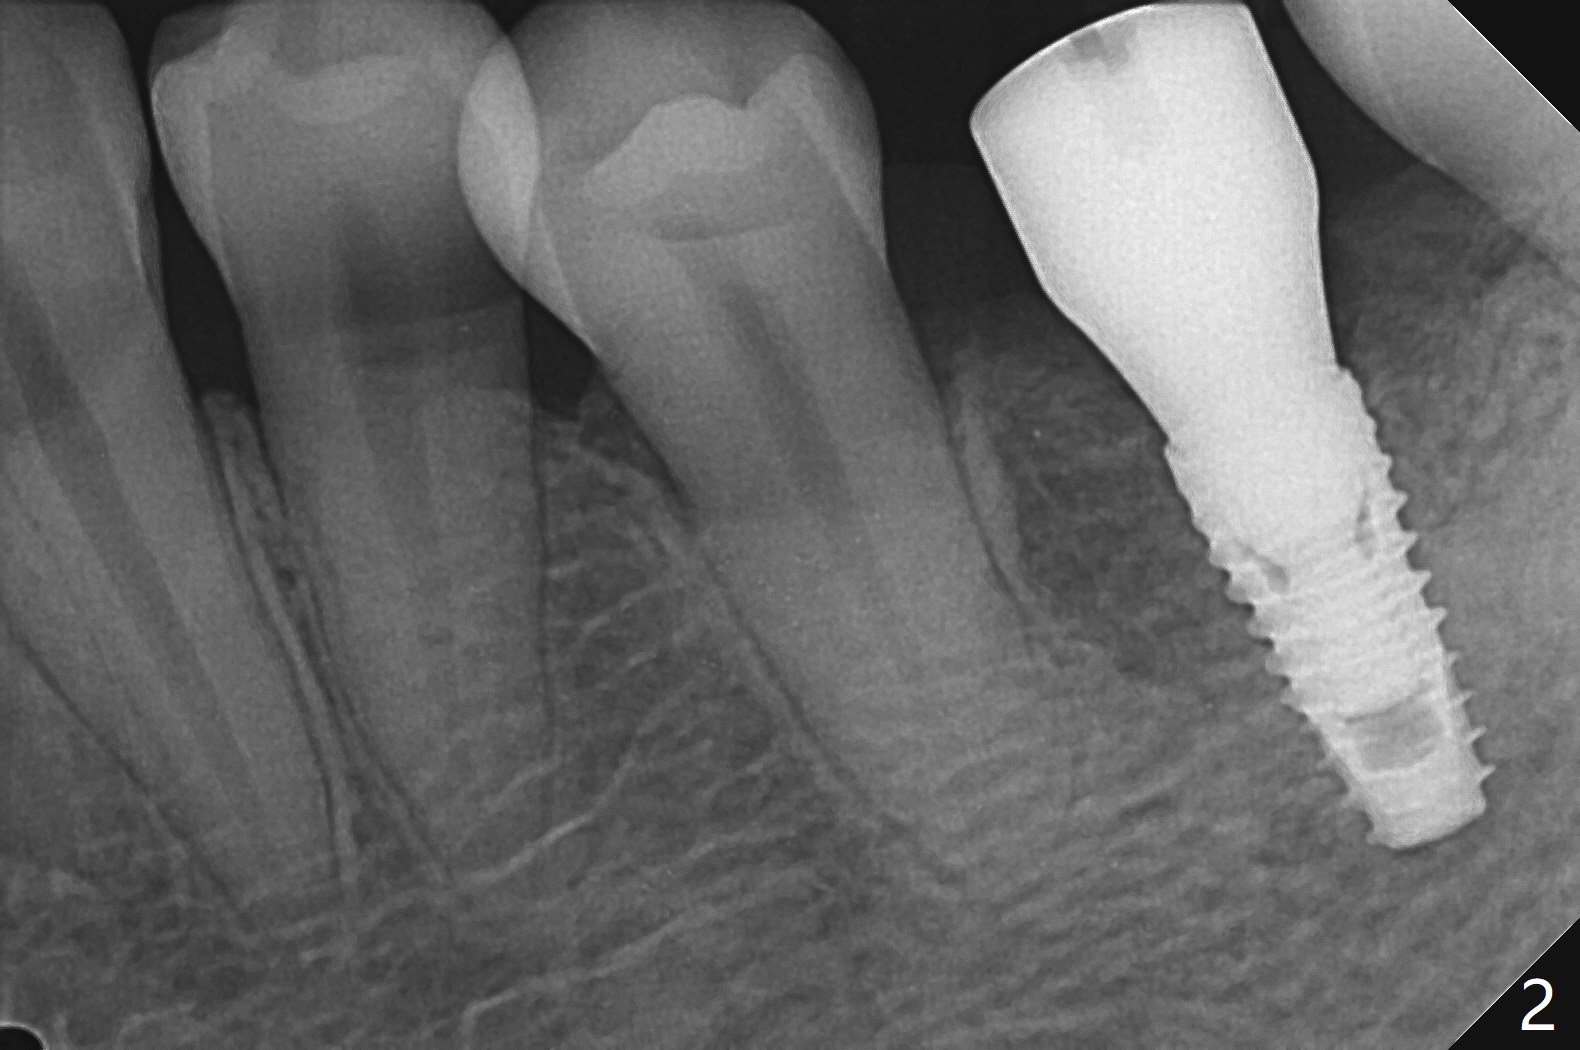

尽管有骨质疏松症,必须使用4.0毫米功螺纹后才能植入3.8x8.5毫米植体。牙周探针检查证实植体近中,远中牙槽嵴下。使用5.5毫米Profile钻头,放置5.5x7(4) 毫米愈合基台,后者好像完全就位(图一,二)。